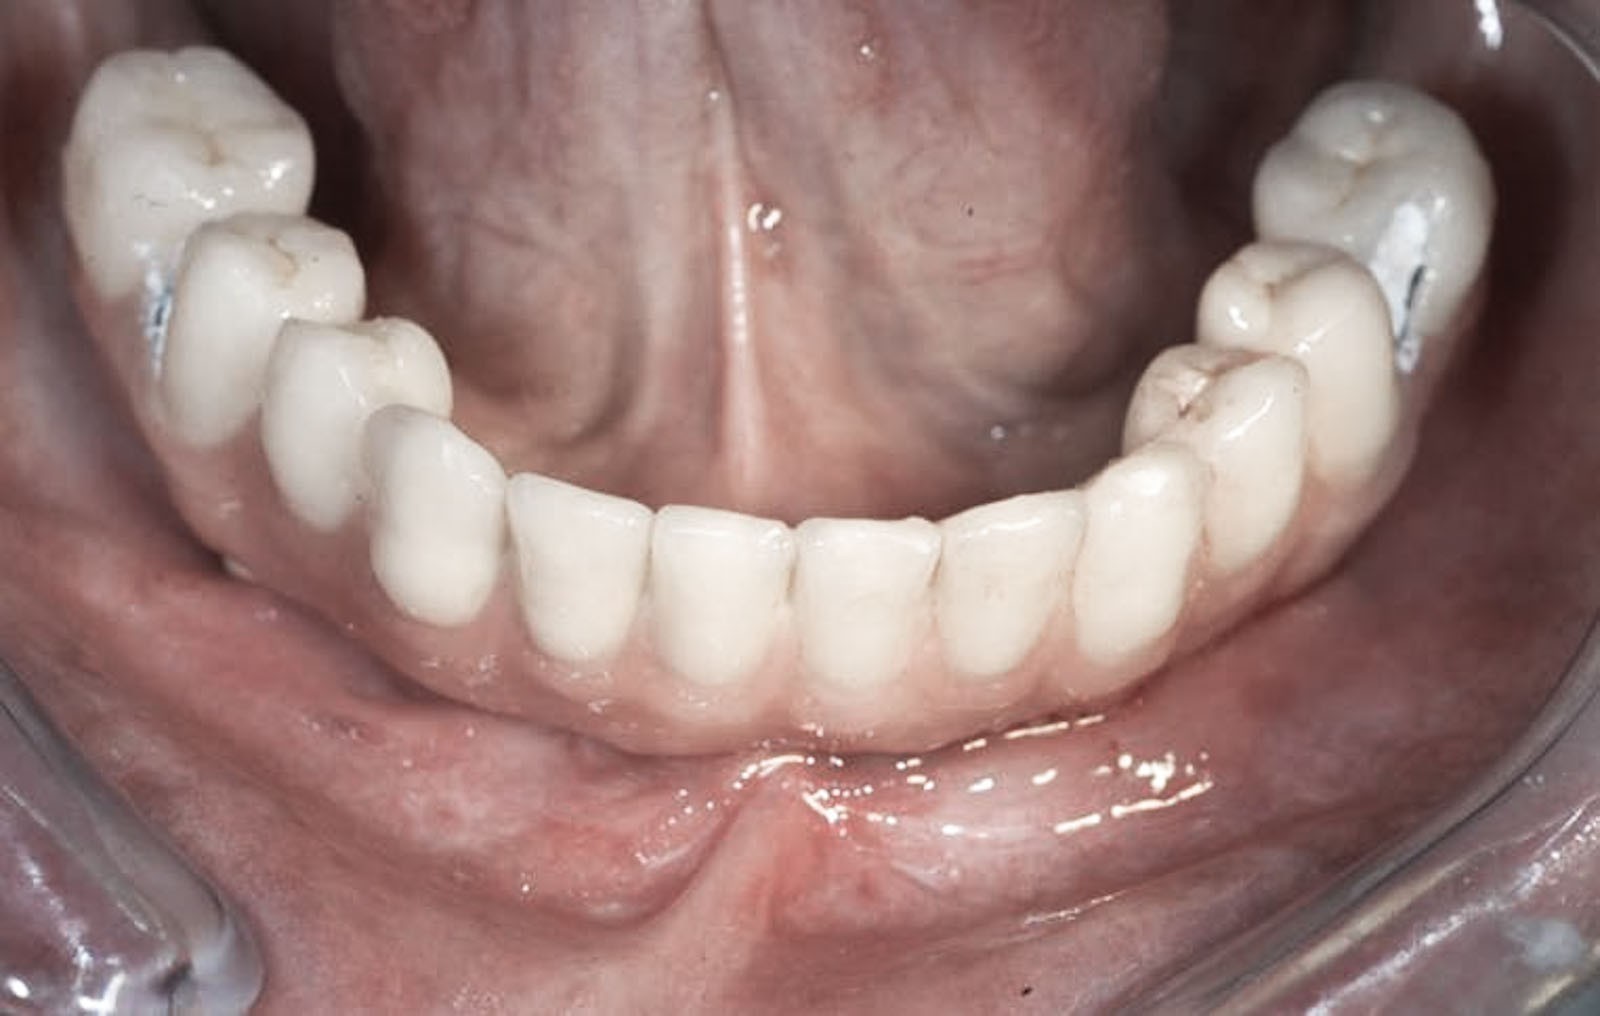

ROZWIĄZANIA PROTETYCZNE ALL-ON-4

Na implantach wszczepionych zgodnie z protokołem all-on-4 możliwe są do wykonania stabilne mosty, jak również ruchome protezy typu nakładowego. Uproszczenie i optymalizacja rozwiązań protetycznych możliwa jest dzięki zastosowaniu kątowych łączników typu MultiUnit (17°, 30°), które po przykręceniu do pochylonych implantów umożliwiają łatwe mocowanie mostu i obsługę serwisową pacjenta.

Przy bezzębiu zawsze istnieje możliwość wykonania uzupełnień protetycznych bez zastosowania implantów i są to całkowite protezy osiadające. W zależności od stanu kości szczęk i żuchwy można wykonać protezy lub mosty mocowane na implantach. Mocowanie protez na implantach może być rozłączne, jak w przypadku protez Overdenture, zwanych również nakładowymi. Oznacza to, że proteza w każdej chwili może być odczepiona od platform implantów przez pacjenta i wyjęta z jamy ustnej. Najbardziej jednak pożądane przez pacjentów rozwiązania protetyczne przy bezzębiu to stabilne, niezdejmowalne mosty, które cementuje się lub przykręca na stałe do implantów. One najlepiej imitują estetykę i funkcję naturalnego uzębienia.

Jest to opatentowana metoda rekonstrukcji implanto-protetycznej kompletnego uzębienia stosowana przy bezzębiu zarówno dla dolnego, jak i górnego łuku zębowego. Bazuje na charakterystycznie wszczepionych 4 implantach zębowych, stąd nazwa Wszystko na 4. Dwa środkowe wprowadzane są w kość prostopadle do jej brzegu i równolegle do siebie, dwa boczne wszczepiane są pod kątem 45 stopni. Rozwiązanie protetyczne to most przykręcany na stałe do implantów, który może być zakładany natychmiast po zabiegu implantacji lub w czasie odroczonym. Gwarancją natychmiastowego przywrócenia funkcji żucia jest odpowiednia siła osadzania implantów mierzona dynamometrycznie w trakcie ich wszczepiania oraz należyta staranność wykonania i osadzenia prac protetycznych.

W zależności od stadium zaniku kostnego mamy różne możliwości implantacji oraz odbudowy kostnej. W ślad za możliwościami implantologicznymi idą rozwiązania protetyczne mniej lub bardziej komfortowe dla pacjenta. Za komfortowe, tym samym optymalne, uznaje się te, które są na stałe montowane na implantach. O możliwości ich zastosowania decyduje rodzaj zastosowanych implantów, ich ilość i rozmiary, siła, z jaką są posadowione w kości, jakość, wymiary oraz fakt, czy była odbudowywana czy tego nie wymagała.